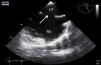

During physical examination, a fixed split second heart sound was heard. Electrocardiography was normal, but transthoracic echocardiography (TTE) showed a flattened interventricular septum, dilated right heart chambers (right ventricle 32 mm, right atrium 44 mm×42 mm), increased systolic pulmonary arterial pressure (50 mmHg), and mild tricuspid regurgitation. Due to suspicion of left-to-right shunting, transesophageal echocardiography (TEE) was performed, which revealed an ostium secundum ASD with a defect dimension of 17 mm (Figure 2, Video 1). No other congenital heart abnormality was identified. The defect was deemed to be suitable for percutaneous transcatheter closure. The procedure was performed under general anesthesia with TEE guidance. A 26 mm ASD septal occluder device (Lifetech Cera ASD Occluder, Occlutech International AB, Helsingborg, Sweden) was deployed under fluoroscopic and TEE guidance (Figure 3, Video 2). Cessation of flow across the interatrial septum was confirmed by TEE prior to final deployment of the device. TTE was performed 24 hours after implantation and confirmed proper positioning of the device with no significant residual shunting. Recovery was uneventful and the patient was discharged from the hospital under antiplatelet therapy.